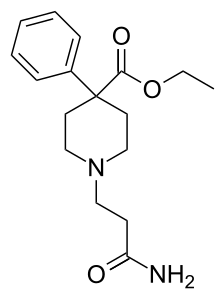

4-Phenylpiperidines

Pethidines (meperidines)

- Pethidine (meperidine)

Structures